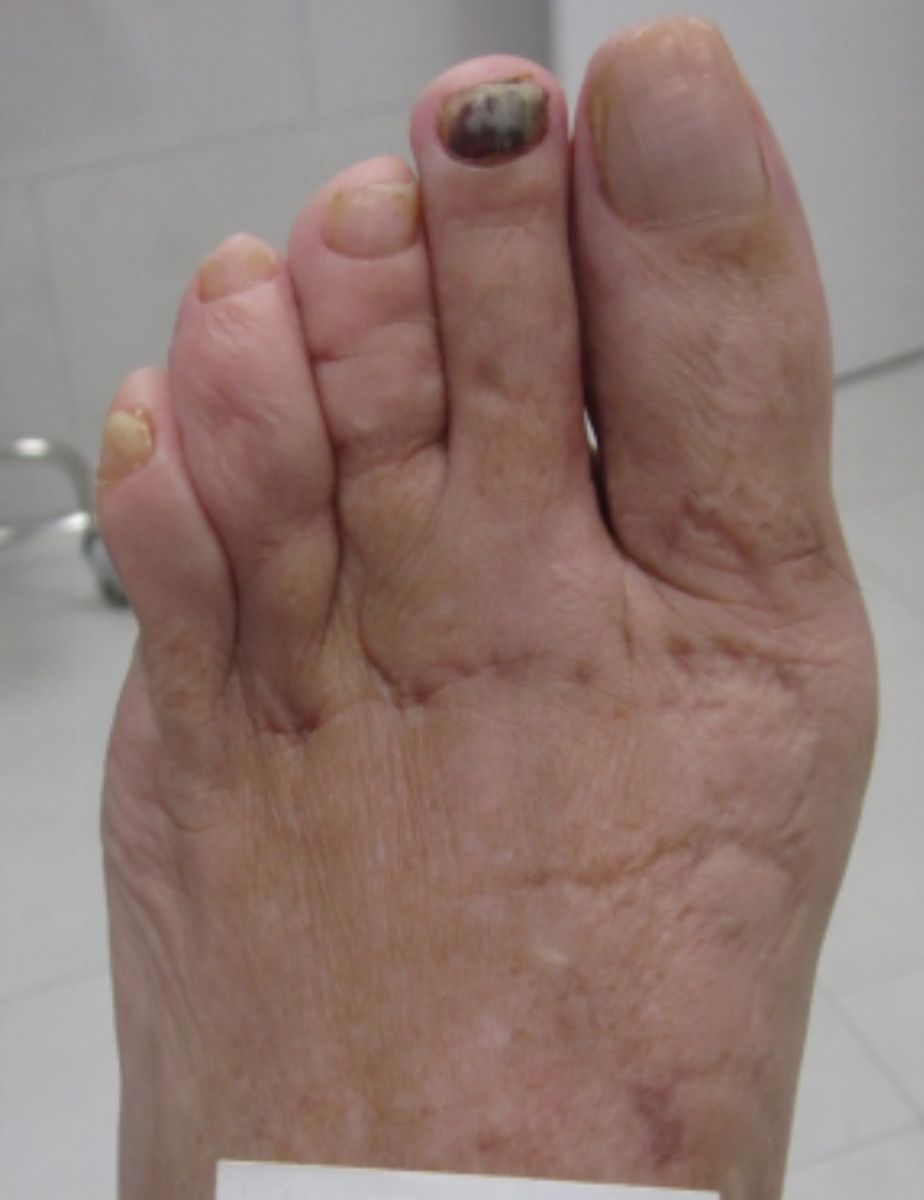

A continuación, mostramos algunas cirugías llevadas a cabo en nuestra clínica podológica.

ANTES

casos reales juanetes alicante (7)

DESPUÉS